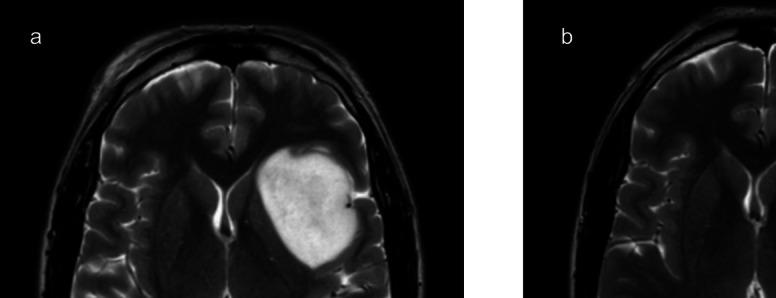

The final items achieved above 80% naming agreement. Object naming proved easier compared to action naming, with accuracy positively influenced by word frequency and negatively affected by the age-of-acquisition variable in both tasks. No subject-related effects were found. Excellent test-retest reliability confirmed the consistency of the tests in measuring language abilities. Positive maps obtained during intraoperative functional mapping demonstrated the sensitivity of the tests in detecting speech-eloquent regions.

最终项目的命名一致性达到80%以上。与动作命名相比,物体命名被证明更容易,在两项任务中,准确率均受到单词频率的正向影响,并受到习得年龄变量的负向影响。未发现与受试者相关的影响。出色的重测信度证实了测试在测量语言能力方面的一致性。术中功能映射期间获得的阳性图谱证明了测试在检测语言表达区域方面的敏感性。